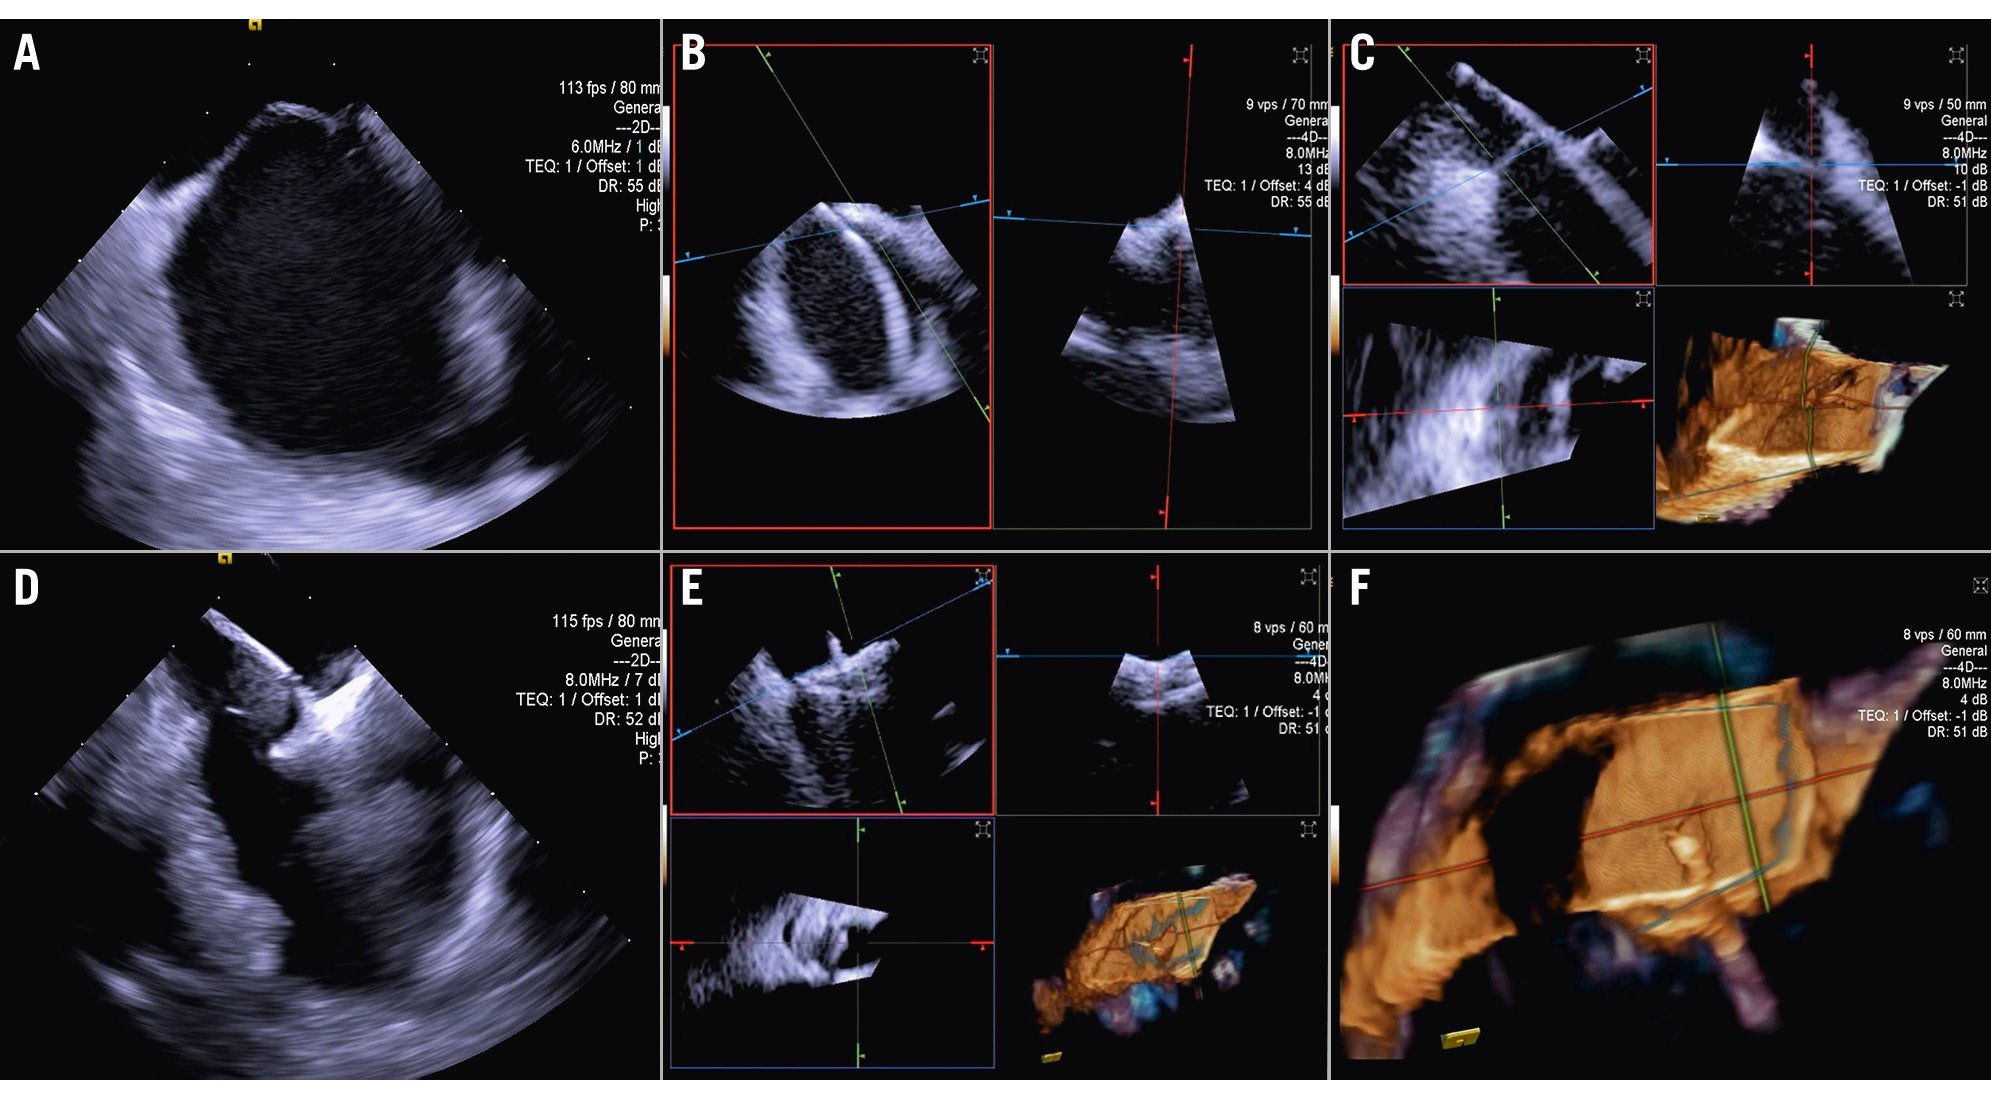

For other procedures, such as transcatheter TV repair or replacement, 3D ICE is typically complementary to TOE16. TOE is the gold standard for TV imaging, but as previously noted, the posterior positioning of the probe relative to the valve can result in far-field tangential views with acoustic shadowing from other heart structures. Given its insertion via the femoral vein and ease of positioning within the right atrium (RA), the 3D ICE probe provides enhanced visualisation of the tricuspid leaflets and annulus (Figure 1, Moving image 1). Nevertheless, it is important to note that despite these advantages, 3D ICE imaging cannot entirely replicate all TOE views, particularly the transgastric short- and long-axis views, underscoring the ongoing clinical utility of TOE in numerous scenarios17. However, this may change in the future, depending on the imaging needed for a specific TV prosthesis implant.

Figure 1. Three-dimensional reconstruction of the atrial view of the tricuspid valve.

When performing a tricuspid TEER procedure (TriClip [Abbott], PASCAL [Edwards Lifesciences]), shadowing from mitral/aortic prostheses, septal hypertrophy, and other factors are particularly problematic when assessing for leaflet insertion. Three-dimensional ICE is a useful alternative for leaflet insertion in edge-to-edge repair. Starting from the home view (right ventricular inflow view), the use of biplane imaging creates a potential grasp view. Subsequently, a live 3D volume image can be obtained and used for a live 3D MPR16. Similar to TOE, 3D ICE also can be used for trajectory and alignment (Figure 4, Moving image 2-Moving image 3-Moving image 4-Moving image 5-Moving image 6-Moving image 7).

Figure 4. Three-dimensional ICE-guided tricuspid transcatheter edge-to-edge repair. A) 3D MPR ICE imaging planes with posterior and anterior leaflets in the TV home view (top left), septal leaflet and anterior/lateral grasping view (top right). The blue plane (bottom left) represents the short-axis (atrial en face) view of the TV leaflets. Finally, the corresponding 3D volume (bottom right; the aorta is at 5 o’clock). B) 3D colour MPR ICE imaging shows severe tricuspid regurgitation, allowing assessment of the number of regurgitation jets and jet location. C-E) The first device is advanced under the tricuspid valve. Clip orientation is optimised to be orthogonal to the coaptation line while the clip position is fine-tuned to the target location, and independent leaflet grasping is performed. F) 3D MPR assessment of second device orientation and location. G) 3D MPR assessment of third device orientation and location. H, I) 3D MPR and colour-flow Doppler final assessment of the devices. 3D: three-dimensional; ICE: intracardiac echocardiography; MPR: multiplanar reconstruction; TV: tricuspid valve